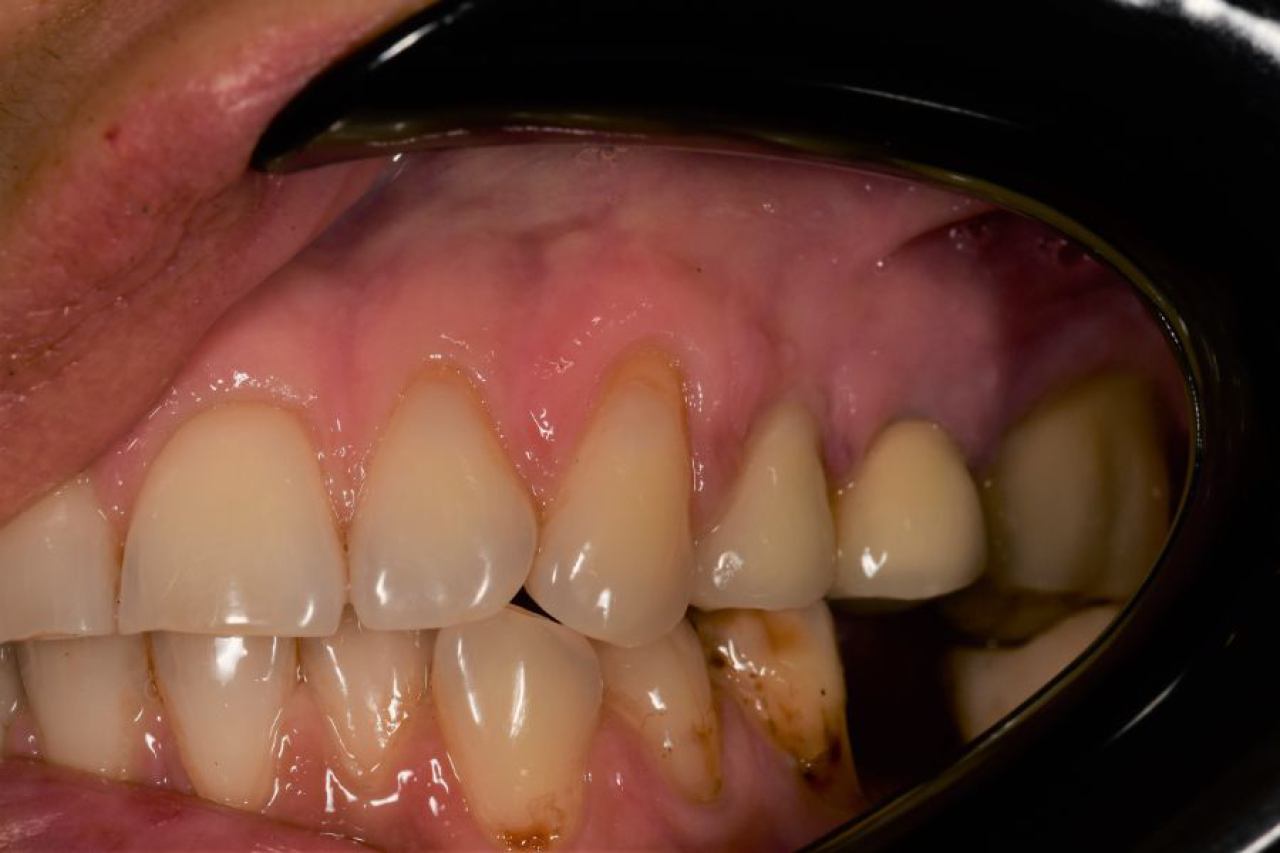

Parodontologija i kirurgija

Parodontologija je grana dentalne medicine koja se bavi zdravljem potpornih struktura zuba (parodonta). Parodont se sastoji od zubnog mesa (gingiva), kosti i vlakana koja vežu zub za kost (parodontalni ligament).

Ovo je grana kojoj Marković Dental Clinic pridaje puno pažnje jer je vrlo kompleksna i bitna za cijelo oralno zdravlje.

Regeneracija kosti i mekog tkiva

Gingivalne recesije u narodu poznatije kao „povlačenje zubnog mesa" moguće je korigirati kirurškim zahvatom te vratiti gingivu (zubno meso) u fiziološki položaj mikrokirurškim tehnikama. Zahvati koje odrađujemo kod regeneracije kosti i mekog tkiva su podizanje dna sinusa (sinus lift) i nadomještanje izgubljenog volumena kosti (augmentacija kosti, regeneracija kosti).